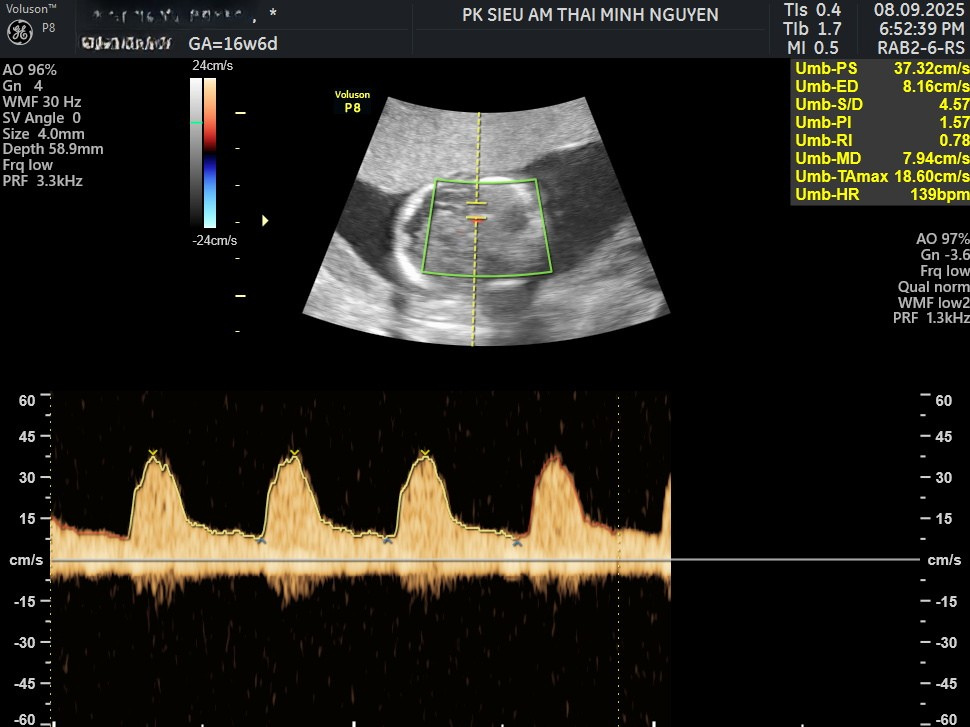

Hiện nay, phương pháp sàng lọc quan trọng nhất là Doppler động mạch não giữa, gọi là MCA-PSV.

Khi thai thiếu máu, máu loãng hơn và vận tốc dòng chảy trong động mạch não giữa tăng lên. Nếu chỉ số vượt 1.5 MoM theo tuổi thai, nguy cơ thiếu máu mức trung bình đến nặng rất cao.

Đây là phương pháp không xâm lấn và được xem là tiêu chuẩn vàng trong sàng lọc thiếu máu thai nhi.

Ngoài Doppler, siêu âm có thể ghi nhận các dấu hiệu gợi ý như tim to, tràn dịch ổ bụng, phù da hoặc nhau dày. Tuy nhiên, nhiều trường hợp chỉ biểu hiện qua Doppler trước khi có phù thai.